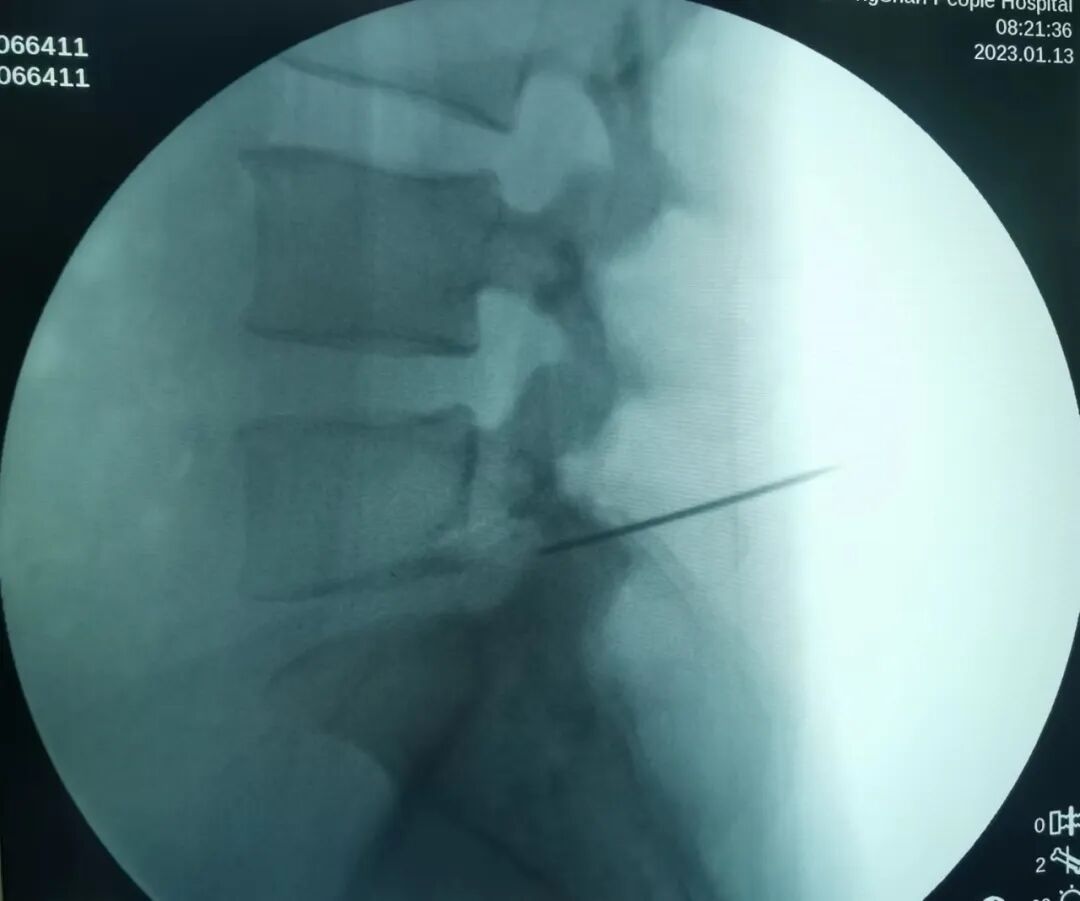

第二步:麻醉穿刺:穿刺点以1%利多卡因混合液2~3mL行局部麻醉,然后穿入18G穿刺针并以1%利多卡因8~10mL麻醉穿刺路径。穿刺至上关节突外侧缘处再次注射6-10ml麻药,这样术中疼痛情况及感受性都会好很多,做一长约1cm的切口

第三步:切开皮肤、置入导丝、扩张通道、建立手术通路

穿刺针尖到达上关节突后,正侧位透视位置难以,通过穿刺针置入导丝并移去穿刺针,置入克氏针确定位置,逐级扩张皮下及筋膜层至关节突外侧缘,随后置入环锯套筒行关节突成形建立手术通道。